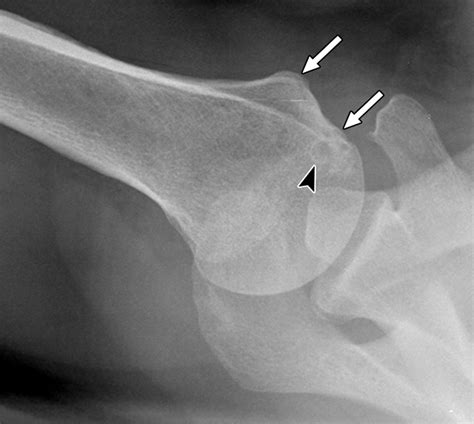

• Calcific Tendonitis: The formation of calcium deposits within the tendons at their insertion point on the greater tubercle, leading to intense pain.

• Subacromial Impingement: A condition where the greater tubercle rubs against the underside of the acromion during elevation, causing irritation to the bursa and tendons.

Diagnostic Imaging and Rehabilitation

Diagnosing issues involving the greater tubercle of humerus typically involves a combination of physical examinations and imaging techniques. X-rays are the gold standard for identifying bony fractures, while MRI scans are essential for visualizing the soft tissues—specifically the rotator cuff tendons—that attach to the bone. Physicians look for irregularities in the bone surface, bone spurs (osteophytes), or evidence of tendon tearing near the insertion sites.